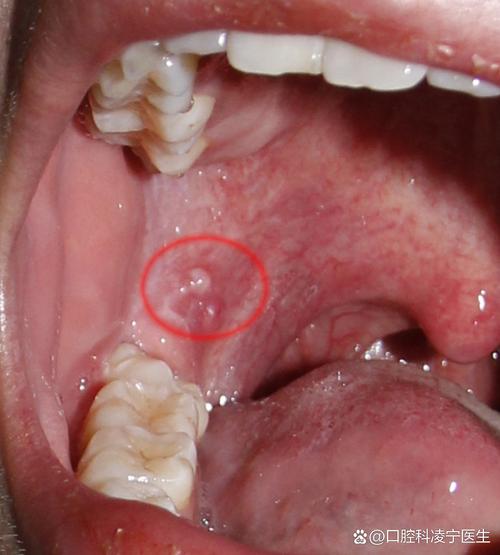

黏液腺囊肿

- 外观:这是最常见的原因之一,通常表现为一个半透明或淡黄色、柔软的小水泡或疙瘩,大小像米粒或绿豆,它可能因为轻微的咬伤、摩擦或导管堵塞而形成。

- 特点:一般不痛,除非它长得比较大或被咬到,它可能会自行变大,然后破裂,流出一些黏稠液体,之后又可能重新长出来。